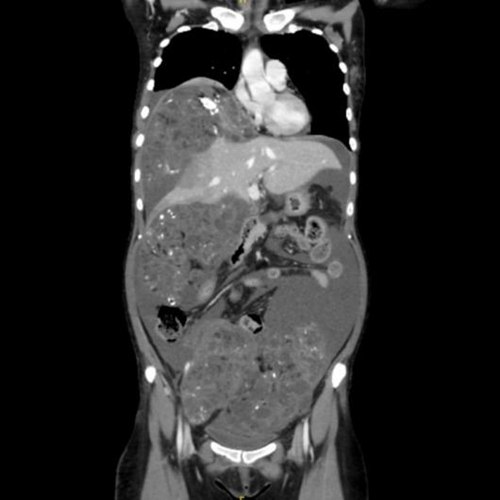

胸腹盆CT检查提示阿丽的肿瘤在盆腹腔广泛转移,巨大包块,大量腹水

2025年8月18日,阿丽再次返院复诊,此时她已经形容枯槁:血红蛋白仅 62g/L(正常成年女性约 110-150g/L),伴水电解质紊乱、凝血异常、低白蛋白血症;影像学明确盆腹腔及腹膜后多发占位增大,肿瘤转移到了肝脏。饱受疾病折磨的阿丽此时已经无法平卧、呼吸急促、腹痛难忍,若再无破局之法,阿丽的生命将进入倒计时。

术中所见触目惊心:阿丽的盆腔积液多达3000ml,20×18×12cm巨大包块侵犯髂外静脉、压迫输尿管,膈肌下及肾隐窝深处均有15cm左右肿物包绕肝脏,肝S4b段转移瘤及多处腹膜转移结节。